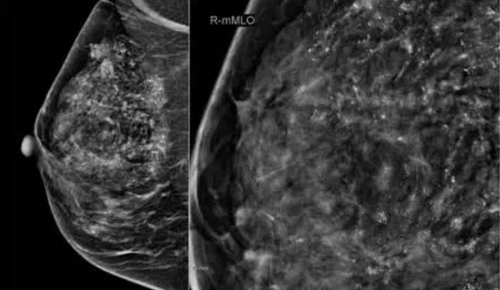

乳腺内点状钙化灶的情况下,说明女性的乳房内有钙质沉积,而且钙化灶有大小之分,同时也分为良性和恶性之分,所以要根据检查结果来做处理,这样才能防止疾病恶化。

如果是因乳腺癌引起的钙化灶,在检查下通常是比较细小的,这需要及时进行治疗才行,防止给女性身体带来更大的伤害,平时也要保持良好的心态,不要太过焦虑压抑,这不仅不利于疾病恢复,还可能会加重症状。